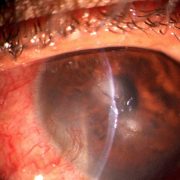

Slitlamp Imaging

Using a beamsplitter, SLR mount and a DSLR camera capture in 18MP (or higher) to get a superior quality image perfect for patient data collection, review and HD live display. Record video clips in full HD.